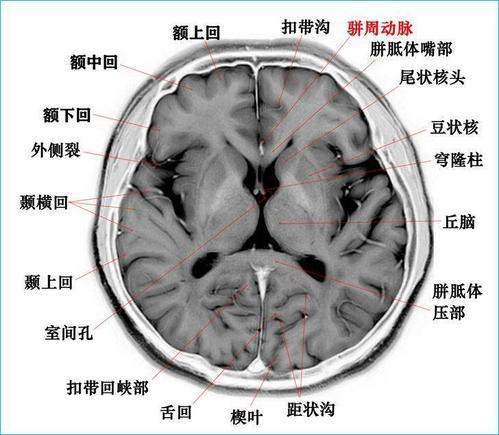

高清mri图颅脑磁共振mri解剖

颅脑磁共振解剖图谱